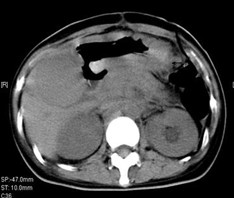

女,40歲,2006年10月底確診為胃腺癌(皮革胃),腹腔淋巴結(jié)轉(zhuǎn)移;2006年11月外科手術(shù)時(shí)見(jiàn)腹腔廣泛轉(zhuǎn)移(粘連),病灶無(wú)法切除(下圖1a,b),預(yù)期生存期低于3個(gè)月;留置(胃)造瘺管。2006年12月開(kāi)始今又生聯(lián)合化療治療,今又生2×1012VP,室溫下自行融化后加入到100ml生理鹽水中,30~40分鐘內(nèi)靜脈滴注完畢,1/次/周,連續(xù)使用6周。今又生給藥三天后靜脈化療。2007年7月外科手術(shù)拔除造瘺管;2007年9月隨訪,患者狀況良好,無(wú)復(fù)發(fā)。

1a 治療前胰腺體部和主動(dòng)脈前方淋巴結(jié)較多較大,胃底和體部較厚僵硬

1b治療后 淋巴結(jié)較少并縮小,胰腺和主動(dòng)脈之間脂肪間隙恢復(fù)清晰,胃底和體部較前變薄,柔軟

2a 治療前 主動(dòng)脈前方,胃底和脾門(mén)之間見(jiàn)大量結(jié)節(jié)狀淋巴結(jié)

2b 治療后 主動(dòng)脈前方,胃底和脾門(mén)之間淋巴結(jié)大部分消失縮小,脂肪間隙較前清晰